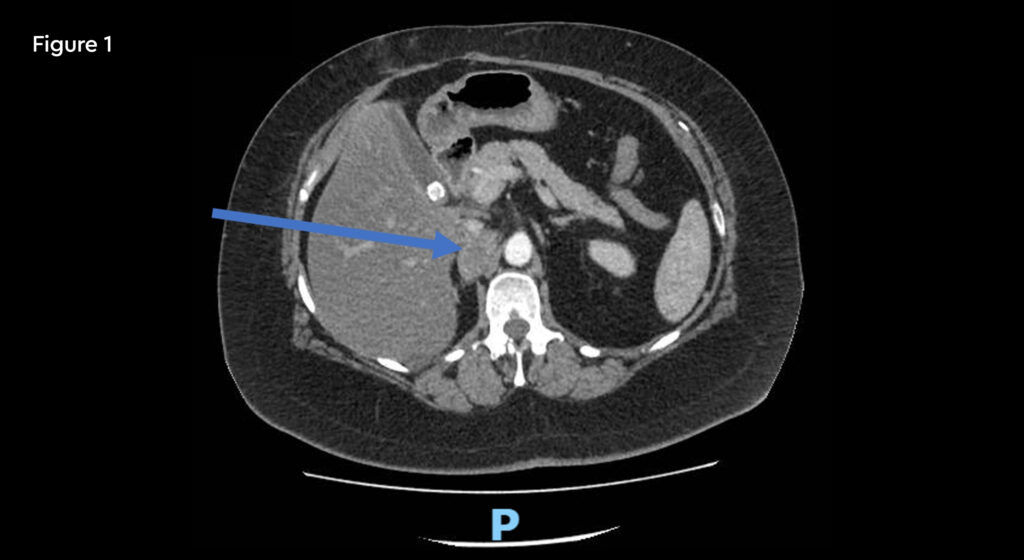

A 52-year-old female with metastatic renal carcinoma. At the time of referral for stereotactic ablative radiotherapy (SABR) she had oligoprogressive disease in a single lymph node beneath the right diaphragmatic crus (figure 1).

Fig 1: Pre-treatment CT scan showing right upper abdominal node measuring 25mm on 10th January 2020

Fig 2: Post-treatment CT scan (19mm) on 12th May 2020 10 weeks after completion of SABR

A follow-up CT scan at 10 weeks after SABR treatment showed a reduction in size of the node.